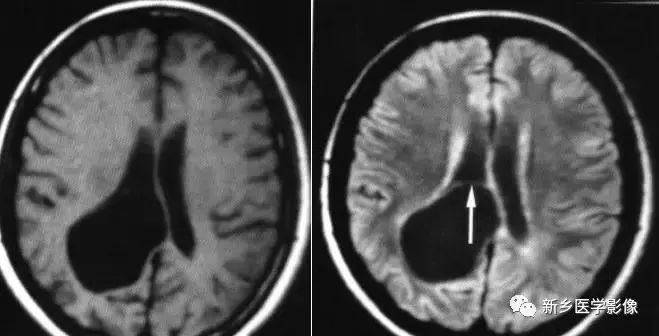

❹ 一侧室间孔阻塞

脑脊液主要产生于脑室的脉络膜丛。当一侧室间孔阻塞时,同侧侧脑室脉络膜丛产生的脑脊液不能进入三脑室,脑脊液在侧脑室内聚积,CT和MR检查表现为一侧侧脑室扩大,扩大明显时可有中线结构向对侧移位,主要原因有室间孔附近的肿瘤、囊肿、囊虫及炎性粘连。

确定一侧侧脑室扩大为室间孔阻塞所致的要点包括:

- 一侧侧脑室扩张明显,有张力;

- 透明隔向对侧移位;

- 扩一大的侧脑室周围没有能够导致该侧侧脑室扩大的其他可以解释的原因。